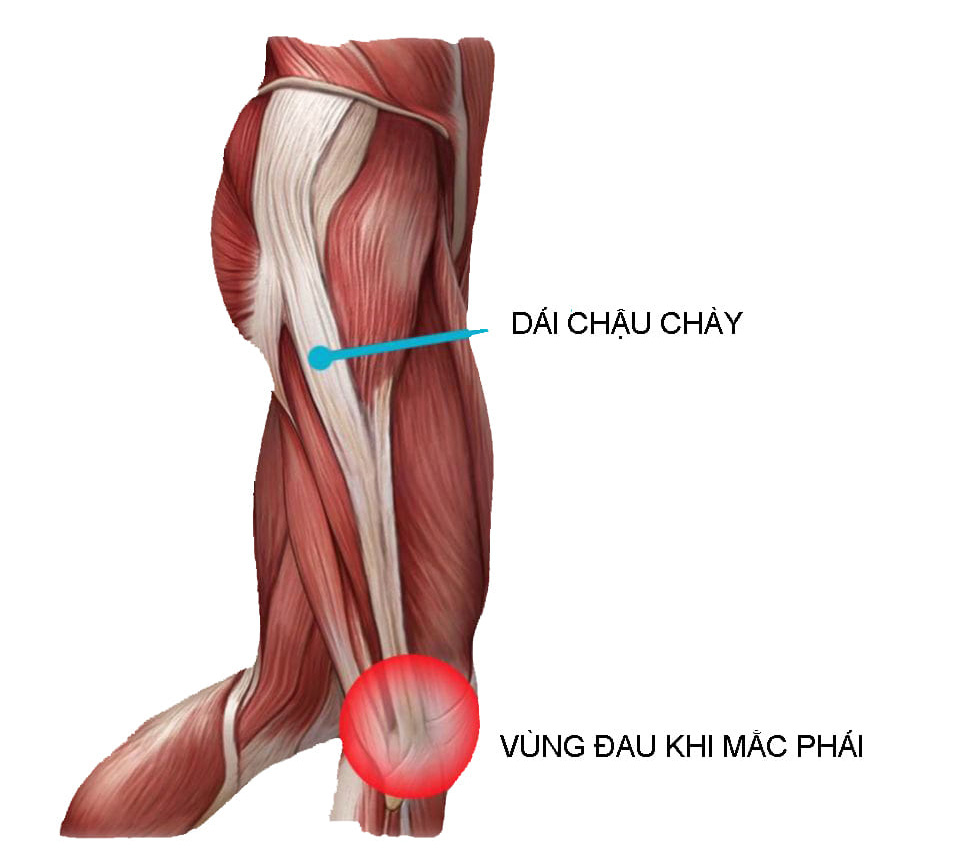

Hội chứng dải chậu chày (IT band)

Đau mặt ngoài gối khi chạy dài hoặc xuống dốc. Liên quan đến kiểm soát hông-gối chưa tối ưu.